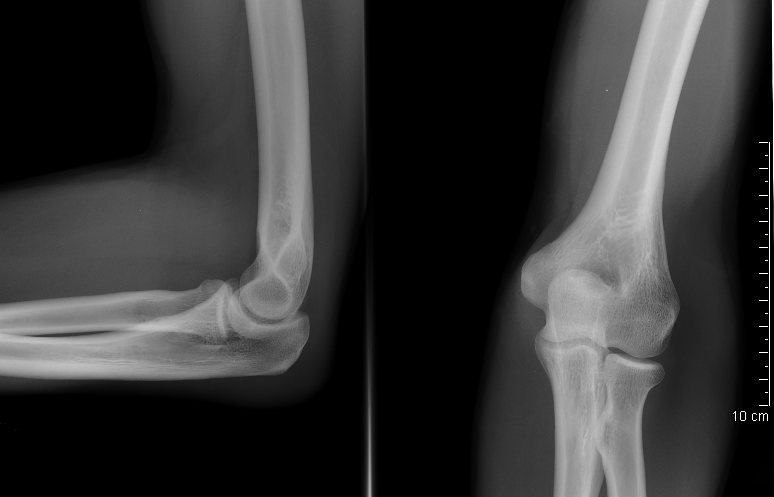

팔꿈치는 상완골, 요골, 척골 사이의 관절로, 굴곡과 신전 운동을 수행한다. 팔꿈치 관절은 상완척골 관절, 상완요골 관절, 근위 요척 관절로 구성되며, 척측 측부 인대와 요골 측부 인대와 같은 인대와 관절낭, 활막, 근육으로 지지된다. 팔꿈치의 기능은 팔을 펴고 구부리며 물건을 잡는 것이며, 굽이각(운반각)이라는 특징을 보인다. 팔꿈치는 유아기부터 청소년기까지 골화 중심의 발달을 거치며, 혈액 공급은 상완 동맥과 그 분지에서, 신경 공급은 근육피부 신경, 정중 신경, 요골 신경, 척골 신경에서 받는다. 팔꿈치 부상은 테니스 엘보, 골프 엘보, 주관절 증후군, 류마티스 관절염, 팔꿈치 탈구, 감염 등 다양한 질환으로 이어질 수 있으며, 사회 문화적으로 다양한 의미를 지닌다.

팔꿉관절(주관절)은 상완골, 요골, 척골 사이에 존재하는 관절이다. 굽힘과 폄(굴신)을 행하는 것은 주로 위팔뼈와 척골 사이이다.

팔꿈치 관절은 공통 관절낭으로 둘러싸인 세 개의 다른 부분으로 구성되어 있다. 이들은 상완의 상완골, 전완의 요골와 척골 사이의 관절이다.| 관절 | 에서 | 로 | 설명 |

| 상완척골 관절 | 자뼈의 도르래절흔 | 상완골의 도르래 | 단순한 경첩 관절로 굴곡 및 신전 운동만 가능하다. |

| 상완요골 관절 | 요골 머리 | 상완골의 작은머리 | 볼 소켓 관절이다. |

| 근위 요척 관절 | 요골 머리 | 자뼈의 요골절흔 | 굴곡 또는 신전의 모든 위치에서 요골은 손을 함께 운반하며 회전할 수 있다. 이 움직임에는 손바닥 엎침과 손바닥 뒤침이 포함된다. |